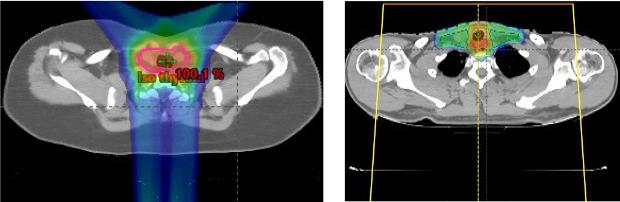

External beam radiotherapy is used in a subset of high-risk patients with differentiated thyroid cancer (DTC). Recurrent, radioactive iodine (RAI)-refractory DTC carries a poor prognosis. We report our initial experience of intensity-modulated proton therapy (IMPT) for recurrent, RAI-refractory DTC.

外照射放疗用于一部分高危分化型甲状腺癌(DTC)患者。复发性、放射性碘(RAI)难治性DTC预后较差。我们报告了调强质子治疗(IMPT)用于复发性、RAI难治性DTC的初步经验。